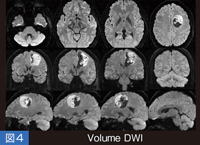

そこでわれわれは、1.6mmの等方性容積データを数分で取得する手法を考案した。これは、1.6mmの薄いスライスによる2Dのacquisitionで、結果として1.6mmのアイソトロピックなボリュームデータが取得できる。これにより、部分容積効果の軽減や、頭蓋底近傍の画像歪みや磁化率アーチファクトの大幅な低減も可能になり、ボリュームデータならではの付加価値を持つこともできる。

実際の、脳腫瘍患者の3方向のMPR像では、頭蓋底近傍の側頭葉や脳幹、小脳などの歪みが大幅に低減している( 図4)。また、color-coded axonographyやDTI tractographyも有用であるほか、近い将来、拡散強調画像を画像統計解析の対象にしていくことも可能になると期待している。

図4